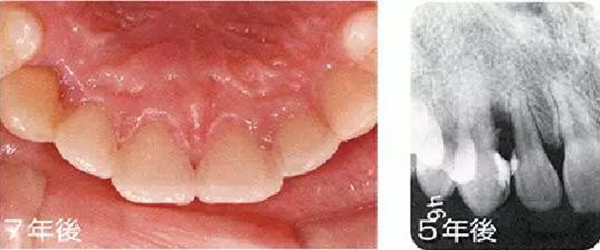

●埋伏齒矯正治療引起的附著喪失

15歲女性。對完全埋伏的右上尖牙進行開窗矯正使得牙齒崩出、整直。矯正結束后已出現(xiàn)7mm的牙周袋,并且有牙周出血現(xiàn)象,X片上也可觀察到骨吸收。推測是由于埋伏引起的偶發(fā)性附著喪失。有必要進行徹底的控制,但在對患者進行說明后沒有獲得理解,中途放棄來院了。

主訴為其他部位而來院時拍攝的X片可觀察到,5年后和7年后的牙周袋雖然沒有大程度惡化,但依然有很深的牙周袋和出血現(xiàn)象。